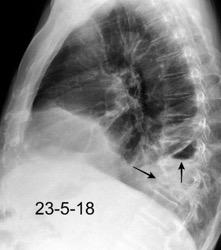

Marzo 2014: Perforación longitudinal distal secundaria a episodio de vómito (síndrome de Boerhaave). Derrame pleural izdo. que evoluciona a empiema.

Wang C-T et al. Tension hydropneumothorax in a Boerhaave syndrome patient: A case report . World J Emerg Med, 2021. Katabathina V et al. Nonvascular, nontraumatic mediastinal emergencies in adults:a comprehensive review of imaging findings. Radiographics. 2011.

Rotura esofágica

Laceración transmural espontánea.

Excesos en comida y/o bebida